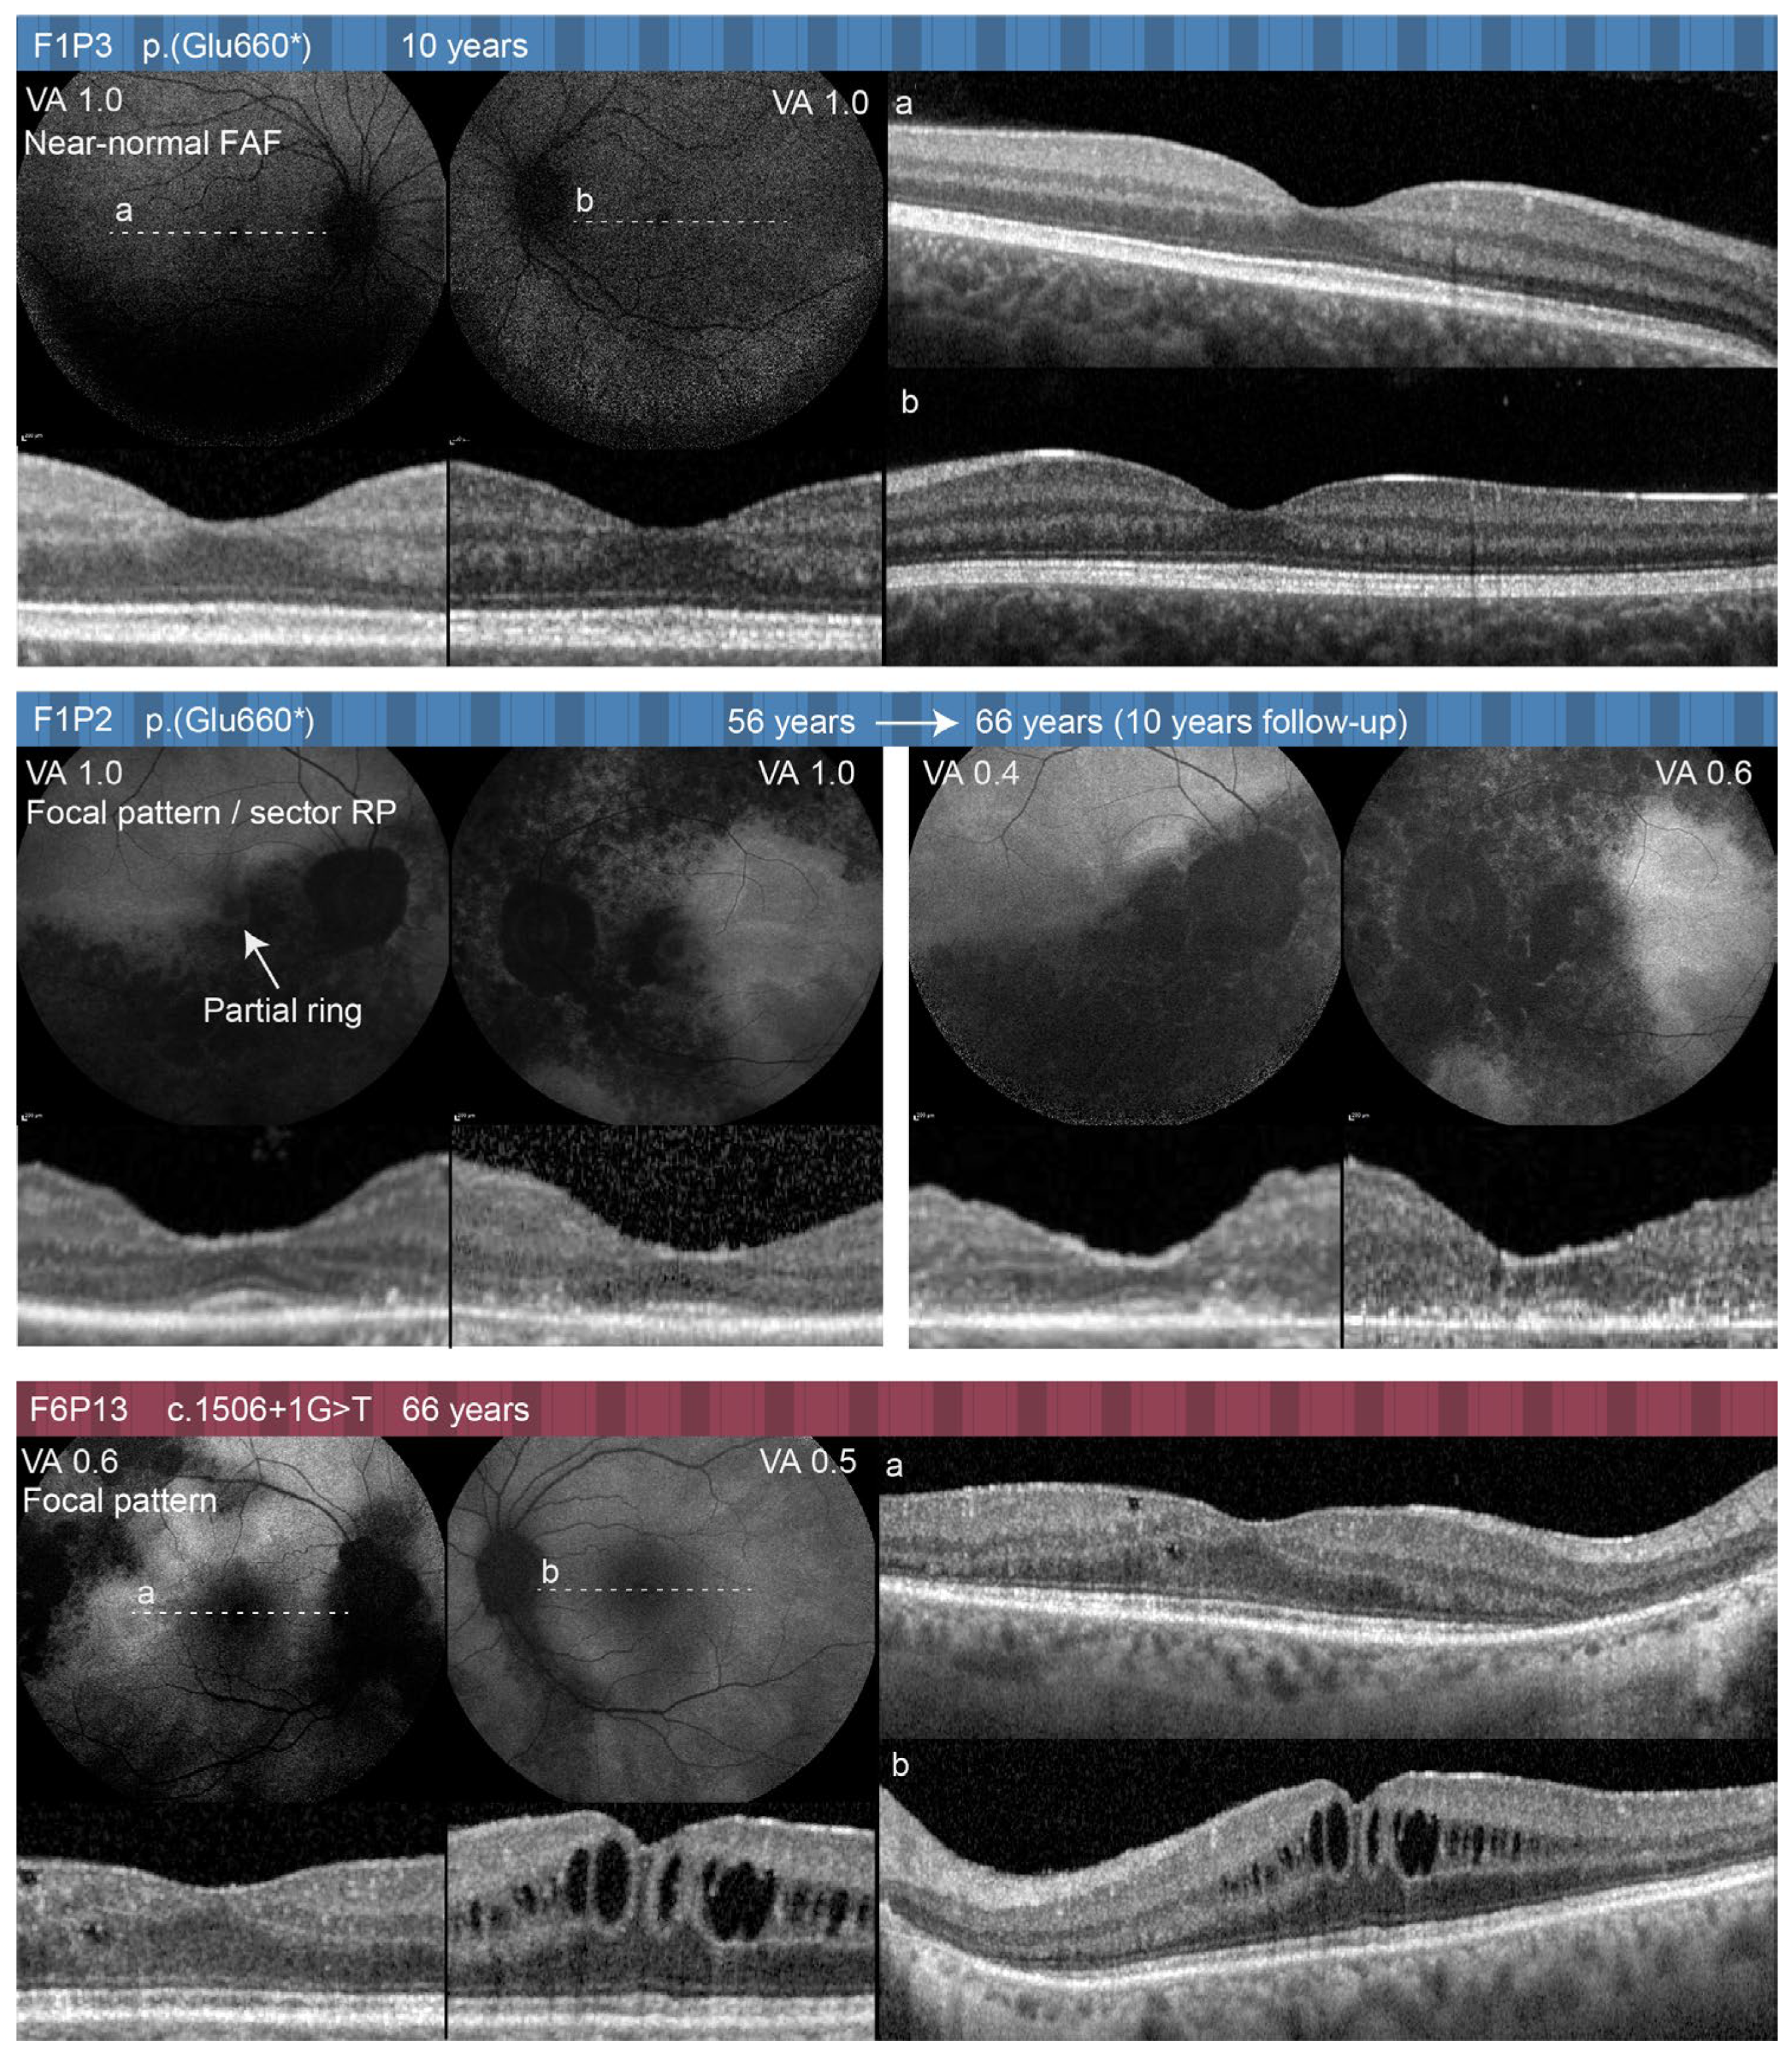

| F1P3 (01072) | F | RPGR-RP | c.1978G>A p.(Glu660*) | No | 10 | Asymptomatic | 15/15 | 0 | 0 | 1.0 (0) | 1.0 (0) | BE: Within normal values; RE: 2932589; LE: 2946630 | BE: Normal | Normal/near-normal pattern BE | BE: Within normal values | N/A | N/A | N/A | N/A | Was not performed |

| F1P2 (00714) | F | RPGR-RP | c.1978G>A p.(Glu660*) | No | 45; 66 | 45 | RE: 6/15 (1/15); LE 3/15 (0/15) | −1.0 (−1.0–0.75/105°) | 0 (+0.750.50/180°) | 1.0 (0); 0.4 (0.39) | 1.0 (0); 0.6 (0.22) | RE: Scotoma in upper half; LE: scotoma in temporal half; RE: 887528; LE: 251130 | BE: Optic pallor, attenuated and sclerotic vessels, maculas without reflex, atrophic central retina, bone spiclues in the peripheral retina | Focal pattern BE (sector RP) | RE: Remnants of ELM in the foveola; LE: absent RPE, Ise, and ELM in the central macula | 68 | 15 | 0.49 (852); 0.11 (246) | 0.25 (446); 0.18 (361) | BE: Reduced and delayed DA and LA ERG; RE: normal PERG P50 and mfERG; LE: reduced/undetectable PERG P50 and mfERG |

| F6P13 (01053) | F | RPGR-RP | c.1506+1G>T | No | 66 | N/A | 12/15 | N/A | N/A | 0.6 (0.22) | 0.5 (0.3) | N/A | BE: Macula without reflex, attenuated vessels, bone spicules in the peripheral retina | Focal pattern BE | BE: Spared ISe, RPE, and ELM in the central macula; CME in the LE | N/A | N/A | N/A | N/A | N/A |